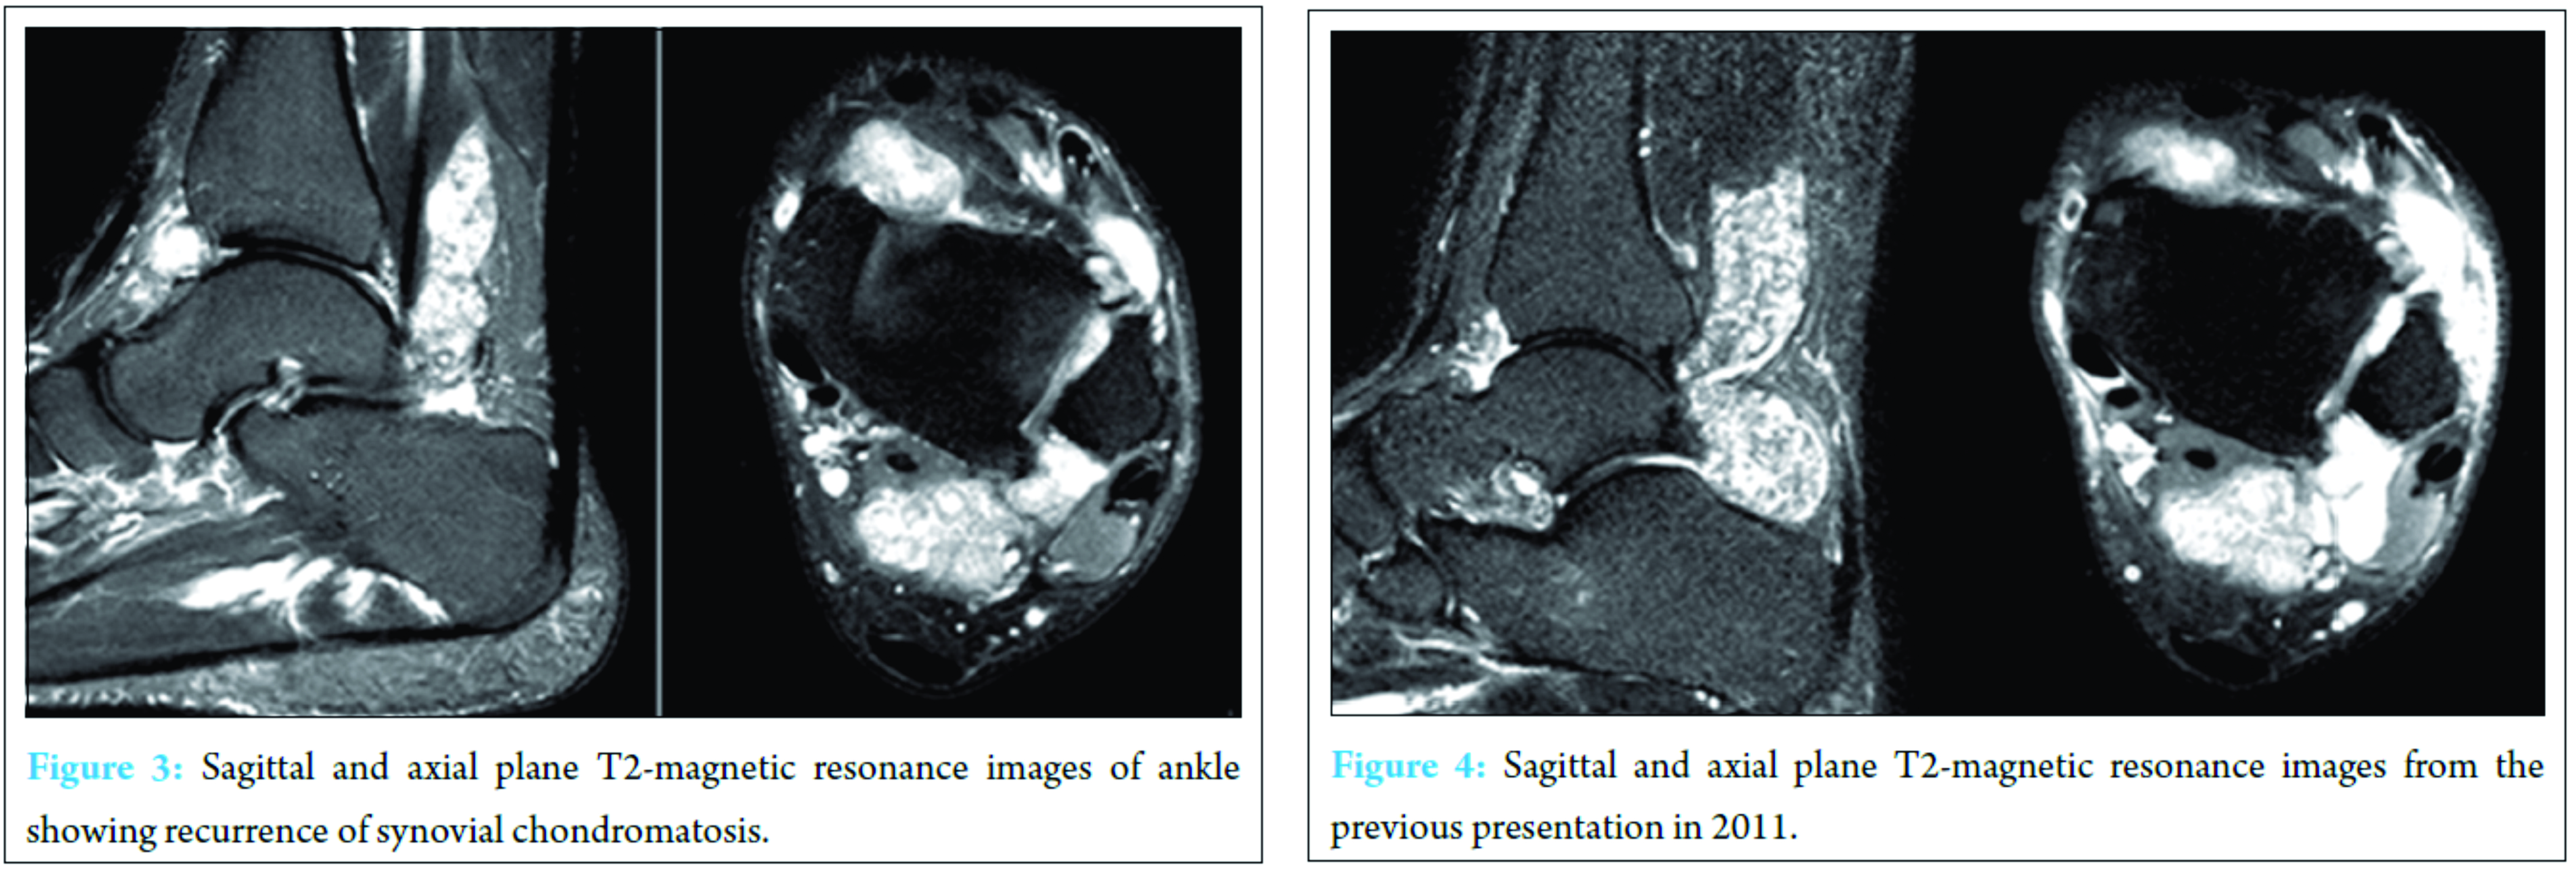

Two years after that first operative intervention, the patient returned with left ankle pain and swelling aggravated by shoe-wearing, weight bearing, and climbing stairs. He also reported symptoms consistent with tarsal tunnel syndrome in the same foot – tingling and burning along the plantar aspect of his foot. Physical examination at this time demonstrated palpable fullness of the ankle joint with minimal restriction in range of motion as well as exquisite tenderness to palpation anterolaterally. A palpable mass was noted along the anterolateral aspect of the ankle. His motor and sensory exams were within normal limits and range of motion of the ankle, and subtalar joints were within normal limits. Radiographs obtained demonstrated opacity overlying the pre-Achilles fat pad and adjacent soft tissues of the posterior ankle (Fig. 1). There was moderate erosion of the anterolateral aspect of the distal tibia. No fractures, dislocations, or intrinsic osseous abnormalities were noted. Ultrasound of the left ankle revealed distention of the joint capsule anteriorly and posteriorly at the tibiotalar joint with intra-articular debris as well as hyperemia of the synovium (Fig. 2). The anterolateral gutter also had intra-articular debris and was distended. Magnetic resonance imagining (MRI) demonstrated numerous large, lobulated, heterogeneously enhancing lesions posteriorly surrounding the flexor hallucis longus (FHL) tendon, and extending into the anterior tibiotalar joint (Fig. 3). There was minimal involvement of the sinus tarsi; however, cranial extension between the distal tibiofibular syndesmosis was noted along with stable erosion of the anterolateral aspect of the distal tibia. The tendons and ligaments of the left ankle were intact, and the articular cartilage was unremarkable. No soft tissue swelling, edema, or bony involvement was identified. These findings were consistent with the MRI findings from his primary presentation 2 years ago (Fig. 4). Extensive ankle joint T2-signal abnormality was consistent with recurrence of synovial chondromatosis. Following this rediagnosis, the patient was scheduled for ankle arthroscopy with joint decompression and synovial debridement.